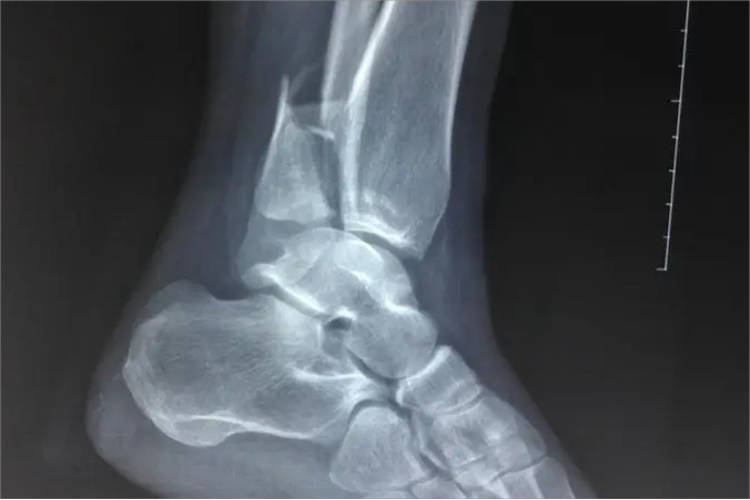

脚踝骨折即踝关节骨折,可出现踝关节的肿胀、疼痛和功能障碍等症状,并出现局部压痛、皮下淤血、畸形和骨擦感等体征。而影像学检查可见前距腓韧带完全断裂,可出现距骨倾斜超过健侧5°~15°,外侧韧带前束和中束断裂可出现距骨倾斜超过健侧15°~30°,外侧韧带的三个组成部分完全断裂,可出现距骨倾斜超过健侧大于30°。

同时,若下胫腓韧带全部断裂时,可出现内踝与距骨间隙增宽超过2~3mm,下胫腓间距大于5mm;下胫腓韧带不全断裂可出现下胫腓间距小于5mm但大于3mm,且对侧下胫腓间隙小于3mm。